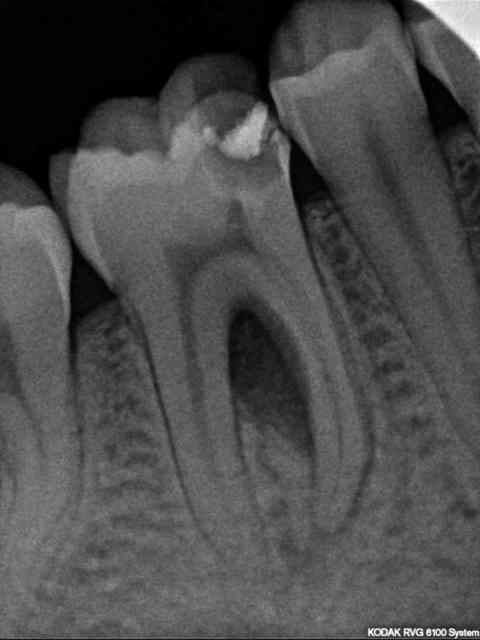

Patient de 22 ans, RAS au niveau général, bonne hygiène.

46 nécrosée avec image de perte osseuse inter-radiculaire. Pas de mobilité, pas d'épisode infectieux aigü.

Que lui proposeriez-vous en 1ère intention ? Uniquement le traitement radiculaire et surveillance de la cicatrisation ou bien d'emblée une chir avec ROG ?

La sémiologie radio indique une lésion combinée endo-paro à point de départ endodontique.

A mon avis, selon un schéma étiologique classique

1-traiter l'etiologie : traitement endodontique

2-réévaluation a 8 semaines de la furcation : pas d'amélioration -> chir paro.

Bien qu'il manque quelques données cliniques : sondage ? modification gingivale ? Pour moi, c'est une lésion purement d'origine endodontique.

Il n'y a aucune perte osseuse inter-dentaire. L'atteinte est inter-radiculaire pure sans communication avec la cavité buccale (si absence de fistule parodontale) et le traitement endodontique, réalisé sous digue bien entendu, suivi d'une restauration coronaire étanche est la solution thérapeutique.

Surtout, il faut éviter toute intervention chirurgicale précipitée, tu as encore, même si elle n'est visible à la radiographie, toute la trame collagénique encore en place. Le potentiel de cicatrisation de ce type de lésion est optimal.

Étonnamment, RAS au sondage paro.

Endo ce jour, sous digue avec irrigation "généreuse" : je regrette d'avoir dépointé le maître-cône distal au dernier moment...

La suite dans 2 mois.

Pas vraiment si c'est une lésion endo pure.

Sans vouloir t'offenser, tu comptes laisser cette obturation coronaire pendant ces deux mois ?? Elle ne semble pas très étanche particulièrement au niveau cervical.